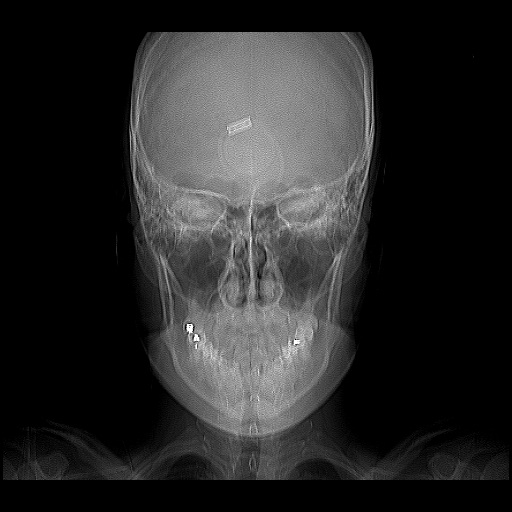

K…..If the shooter then shoots himself then he was trained under Project Monarch and is usually chipped 0- usually in the Underground Base just East of Vancouver, Canada.

Chipped Individual trained by the NSA…